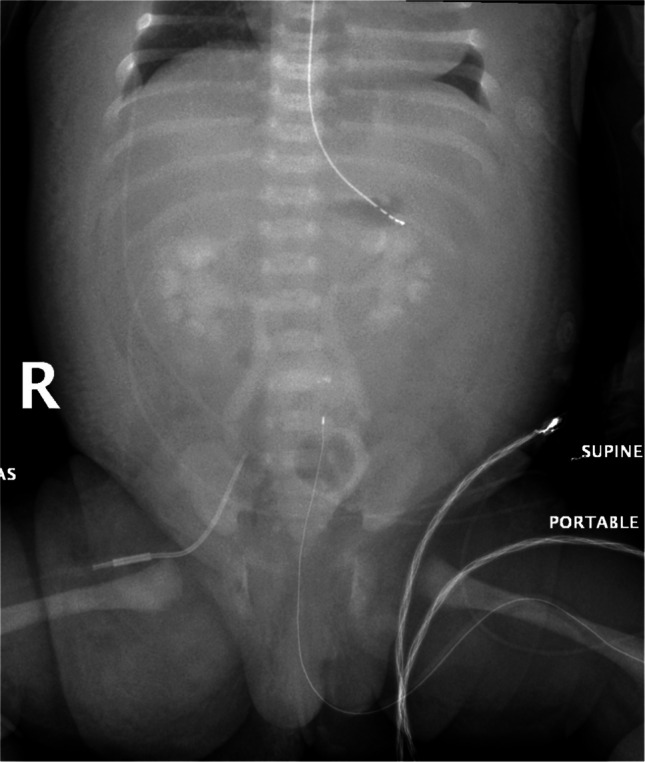

背景:弥漫性浆膜和软组织增强是婴儿心导管置入术后罕见的影像学现象。浆膜和软组织增强的外观可以模拟气腹,可能导致误诊和不必要的诊断程序。虽然病例报告中记录了浆膜和软组织增强,但没有研究系统地评估与其发展相关的危险因素。目的:确定婴儿心导管术后浆膜及软组织强化的频率,并确定与此现象相关的临床及影像学因素。材料和方法:本回顾性研究分析了2010年1月至2019年9月期间在我院接受心导管插入术的婴儿。手术后2天内获得的腹部x线片由三名儿科放射科医生独立审查是否存在浆膜和软组织增强。从电子病历中提取临床数据,包括对比剂、肾功能和心脏生理学。统计分析包括t检验和逻辑回归,以确定与浆膜和软组织增强相关的因素,并使用Fleiss kappa检验评估观察者间的信度。结果:在1796名接受心导管插入术的婴儿中,294名接受了腹部x线片随访。在21例(7.1%)患者中,所有三名放射科医生均发现浆膜和软组织增强。与浆膜和软组织增强相关的重要因素包括插管前和插管后肌酐水平较低(术前0.36±0.17 vs 0.46±0.30 mg/dL;P = 0.043;后0.35±0.11 vs 0.45±0.29 mg/dL;P=0.009),对比度更高(31.8±21.4 vs 21.0±18.1 mL;P=0.013),单位体表面积造影剂体积更高(123.0±69.2 vs 80.8±56.2 mL/m^2;P = 0.002)。浆膜和软组织增强在双心室心脏生理患者中更常见(125/294;42.5%比169/294;57.5%)。结论:一小部分新生儿心导管术后出现浆膜和软组织增强,并与较高的造影剂剂量和体表面积调整的造影剂体积有关。儿科放射科医师对浆膜和软组织增强的认识有助于避免气腹的误诊。

Background: Diffuse serosal and soft tissue enhancement is a rare imaging phenomenon observed in infants following cardiac catheterization. The appearance of serosal and soft tissue enhancement can mimic pneumoperitoneum, potentially leading to misdiagnosis and unnecessary diagnostic procedures. While serosal and soft tissue enhancement has been documented in case reports, no studies have systematically evaluated the risk factors associated with its development.

Objective: To determine the frequency of serosal and soft tissue enhancement in infants following cardiac catheterization and identify clinical and imaging factors associated with this phenomenon.

Results: Among 1,796 infants who underwent cardiac catheterization, 294 had follow-up abdominal radiographs. Serosal and soft tissue enhancement was identified as present by all three radiologists in 21 patients (7.1%). Significant factors associated with serosal and soft tissue enhancement included lower pre- and post-catheterization creatinine levels (pre- 0.36 ± 0.17 vs 0.46 ± 0.30 mg/dL; P=0.043; post- 0.35 ± 0.11 vs 0.45 ± 0.29 mg/dL; P=0.009), higher contrast volume (31.8 ± 21.4 vs 21.0 ± 18.1 mL; P=0.013), and higher contrast volume per body surface area (123.0 ± 69.2 vs 80.8 ± 56.2 mL/m^2; P=0.002). Serosal and soft tissue enhancement occurred more frequently in patients with bi-ventricular cardiac physiology (125/294; 42.5% compared to 169/294; 57.5%).

Conclusion: Serosal and soft tissue enhancement occurs in a small proportion of neonates following cardiac catheterization and is associated with higher contrast dosages and body surface area-adjusted contrast volumes. Awareness of serosal and soft tissue enhancement among pediatric radiologists is helpful to avoid misdiagnosis of pneumoperitoneum.